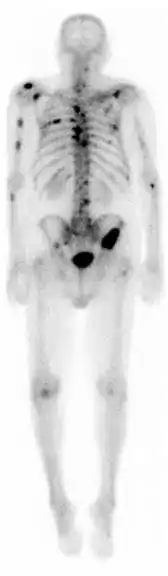

Una gammagrafía ósea es una prueba de medicina nuclear para encontrar ciertas anormalidades en los huesos. Se utiliza sobre todo para ayudar a diagnosticar: cáncer de los huesos o cáncer que se ha diseminado (metástasis) hasta el hueso, la localización de algunas fuentes de inflamación en los testículos (por ejemplo, dolor óseo, tales como dolor de espalda debido a una fractura), el diagnóstico de las fracturas que pueden no ser visibles en las tradicionales imágenes de rayos X, y la detección de daños en los huesos debido a ciertas infecciones y otros problemas.

Las gammagrafías óseas en medicina son un método más de una serie de métodos de formación de imágenes óseas, los cuales se utilizan para detectar visualmente anormalidades óseas. Este tipo de estudios por imágenes incluyen imágenes por resonancia magnética (RMN), tomografía computarizada (TC), radiografía simple y en el caso de la medicina nuclear "gammagrafías óseas". Sin embargo, una gammagrafía ósea es una prueba funcional, lo que significa que mide un aspecto del metabolismo óseo o remodelación ósea, lo que las otras técnicas de imagen no hacen. La gammagrafía ósea nuclear compite con el PET (Tomografía de emisión de positrones) para ver el metabolismo anormal de los huesos, pero la ventaja de la gammagrafía es que es considerablemente menos costoso.

En general, lo que se busca con esta prueba diagnostica son imágenes de hipercaptación que pueden ser localizadas, múltiples o difusas. Cuando son difusas recibe el nombre de superscan. Las imágenes de hipocaptación son más raras. El aumento de captación ósea puede ser por cuatro motivos: el aumento de la formación osteoide, una mineralización ósea aumentada, un aumento de la vascularización, del flujo sanguíneo, o por una denervación simpática.

La técnica en sí consiste en la administración intravenosa de 10-20 milicurios de 99mTc-MDP (Metilén difosfonato) o de 99mTc-HEDP (Hidroxi-Etilén-difosfonato). Tras 2-5 horas postinyección se realiza la adquisición de las imágenes de cuerpo entero, que se llama rastreo anterior y rastreo posterior. Eventualmente, estos rastreos de cuerpo entero se pueden complementar con: gammagrafías localizadas de huesos concretos, SPECT muy útil en columna vertebral y pelvis o gammagrafía ósea de tres fases.